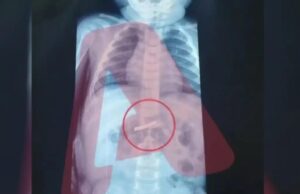

Αγωνιά για 3χρονο που κατάπιε ξυραφάκι – νοσηλεύεται στο Παίδων

Σοβαρό περιστατικό συνέβη στο Νοσοκομείο "Παίδων" όταν ένα τρίχρονο αγοράκι μεταφέρθηκε εσπευσμένα καθώς είχε καταπιεί ξυραφάκι.

Σύμφωνα με τις πρώτες πληροφορίες, το παιδάκι μεταφέρθηκε άμεσα για...